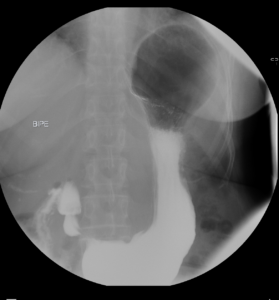

Tránsito EGD